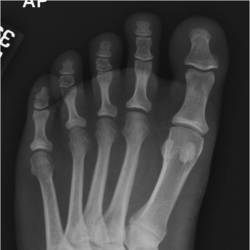

Physician Assistant Lower Limb and Thorax Written Examination - Radiology Pool

Gallery of Unlabled Radiographs from Lecture (Dr. French) - 2020

Click a thumbnail to enter the gallery display. Click the file name link at the bottom left of the gallery display to view the image at high resolution.